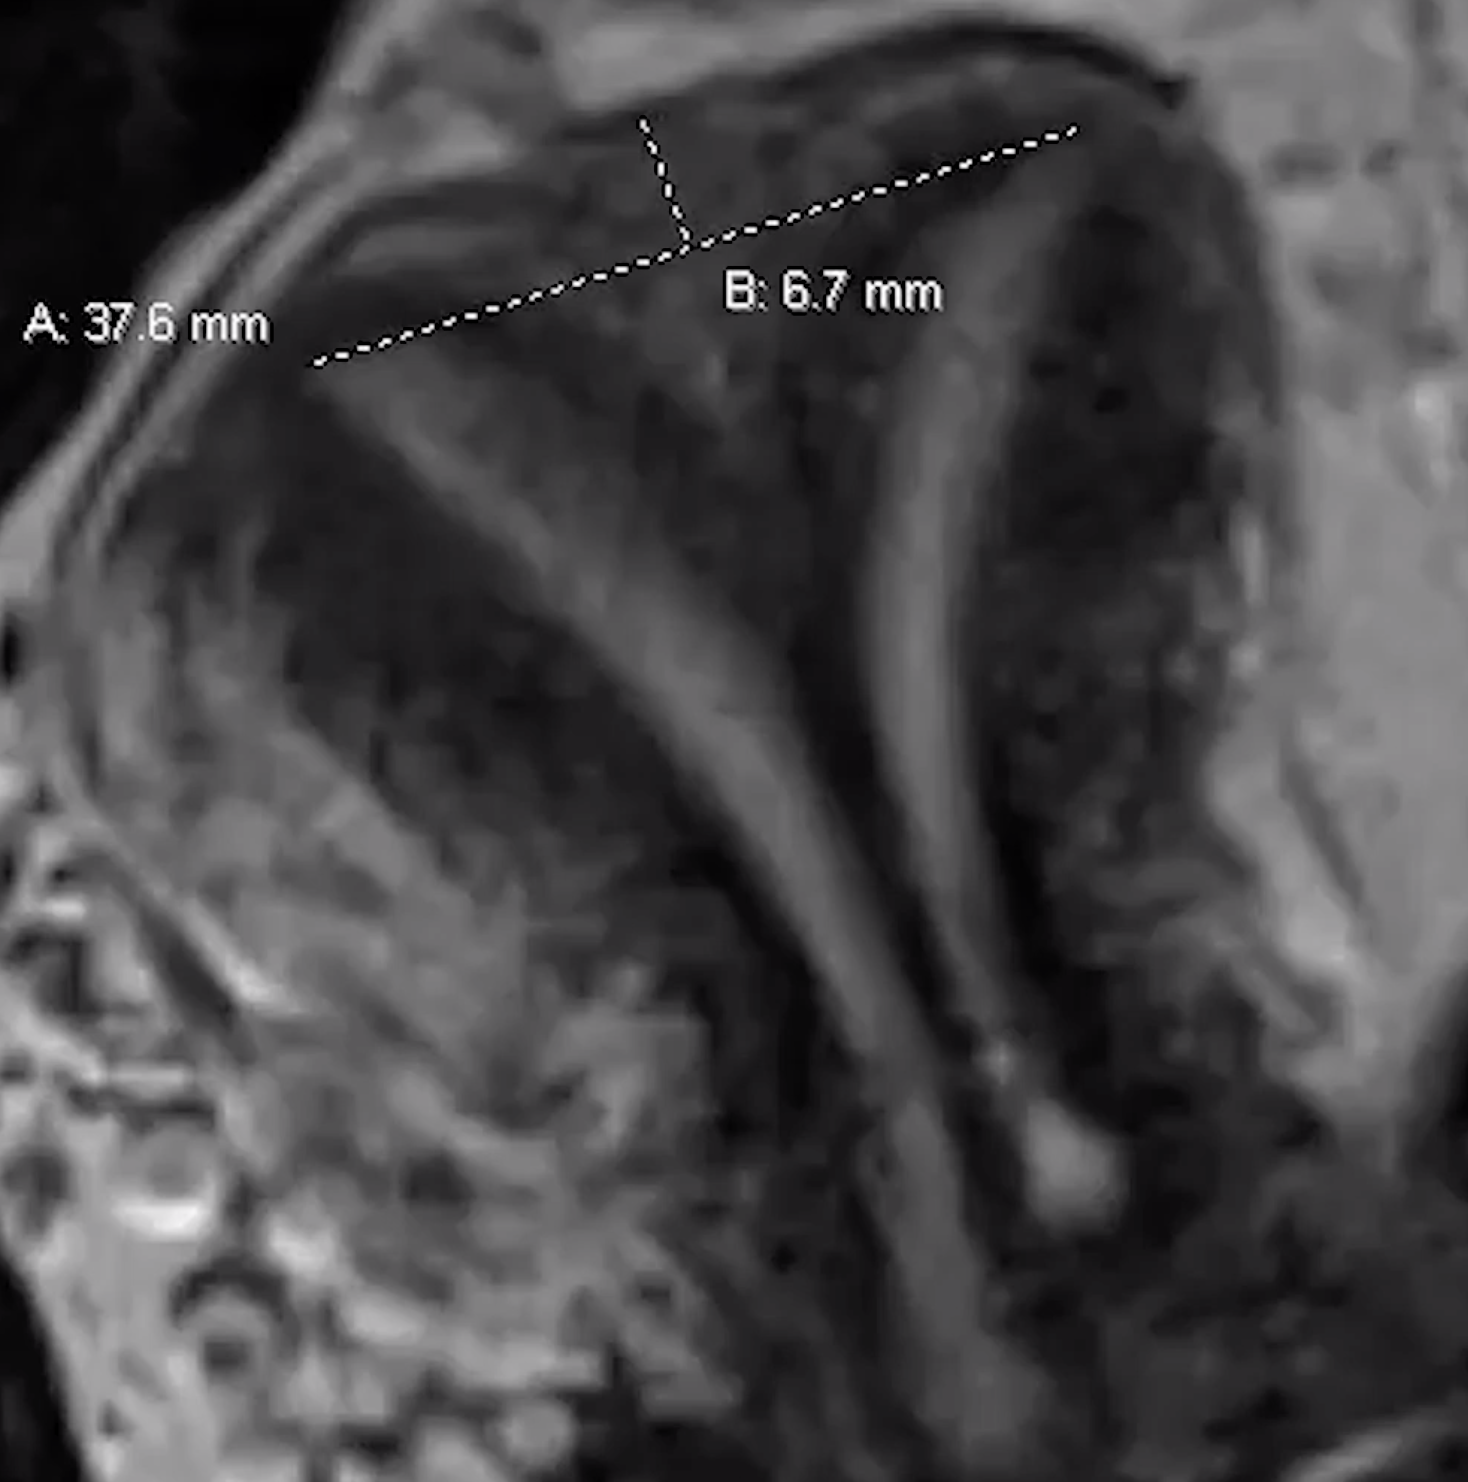

• Septate line

• Drawn line across top of two tips (inter-cornuate line) and another from that line to the fundus

• Needs to be > 5mm to be a septate uterus